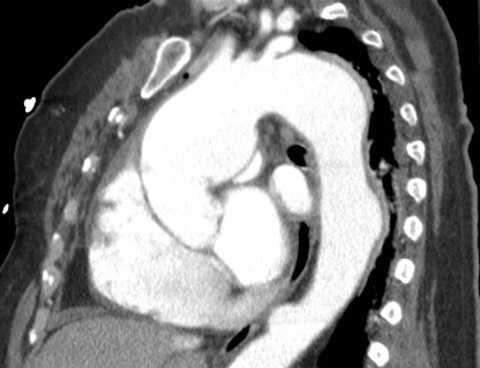

- Компьютерная томография позволяет сделать трехмерную (3D) реконструкцию всей аорты и оценить ее состояние на любом участке.

- Компьютерная томография. КТ (МСКТ) грудной/брюшной аорты позволяет точно и наглядно представить аневризматическое расширение, выявить наличие расслоения и тромботических масс, парааортальной гематомы, очагов кальциноза.

- Томография. КТ (МСКТ) грудной аорты с контрастированием позволяет наглядно выявить мешотчатое или веретенообразное расширение просвета аорты, наличие тромботических масс, расслоения, парааортальной гематомы, очагов кальциноза. Дифференциальный диагноз аневризмы дуги аорты следует проводить с опухолями легких и средостения.